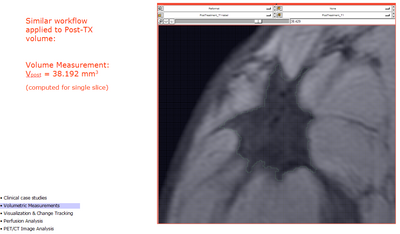

Volumetric Measurement (from draft slides)

defining VOI for measurements

pre-TX statistics

post-TX statistics

pre- versus post-TX statistics

Volume Measurements Workflow

• Measure:

• Volume(t1) and Volume(t2) Question: which is preferred, mm^3!

• Relative % difference

• Absolute change (same units as above)